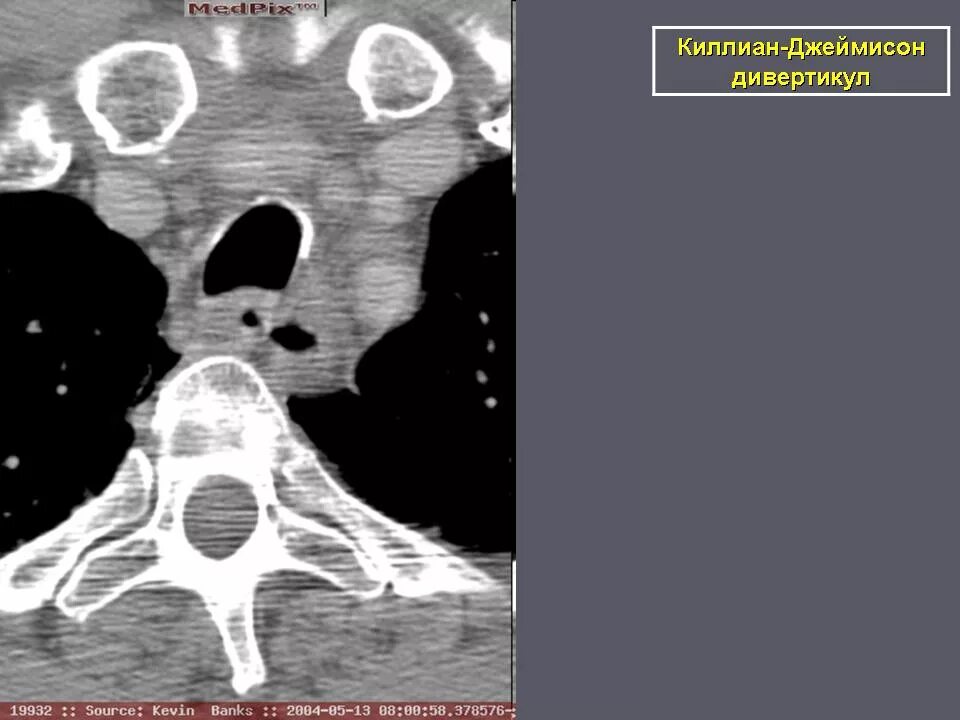

Дивертикул трахеи